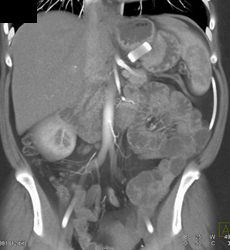

1 Cm GIST Tumor